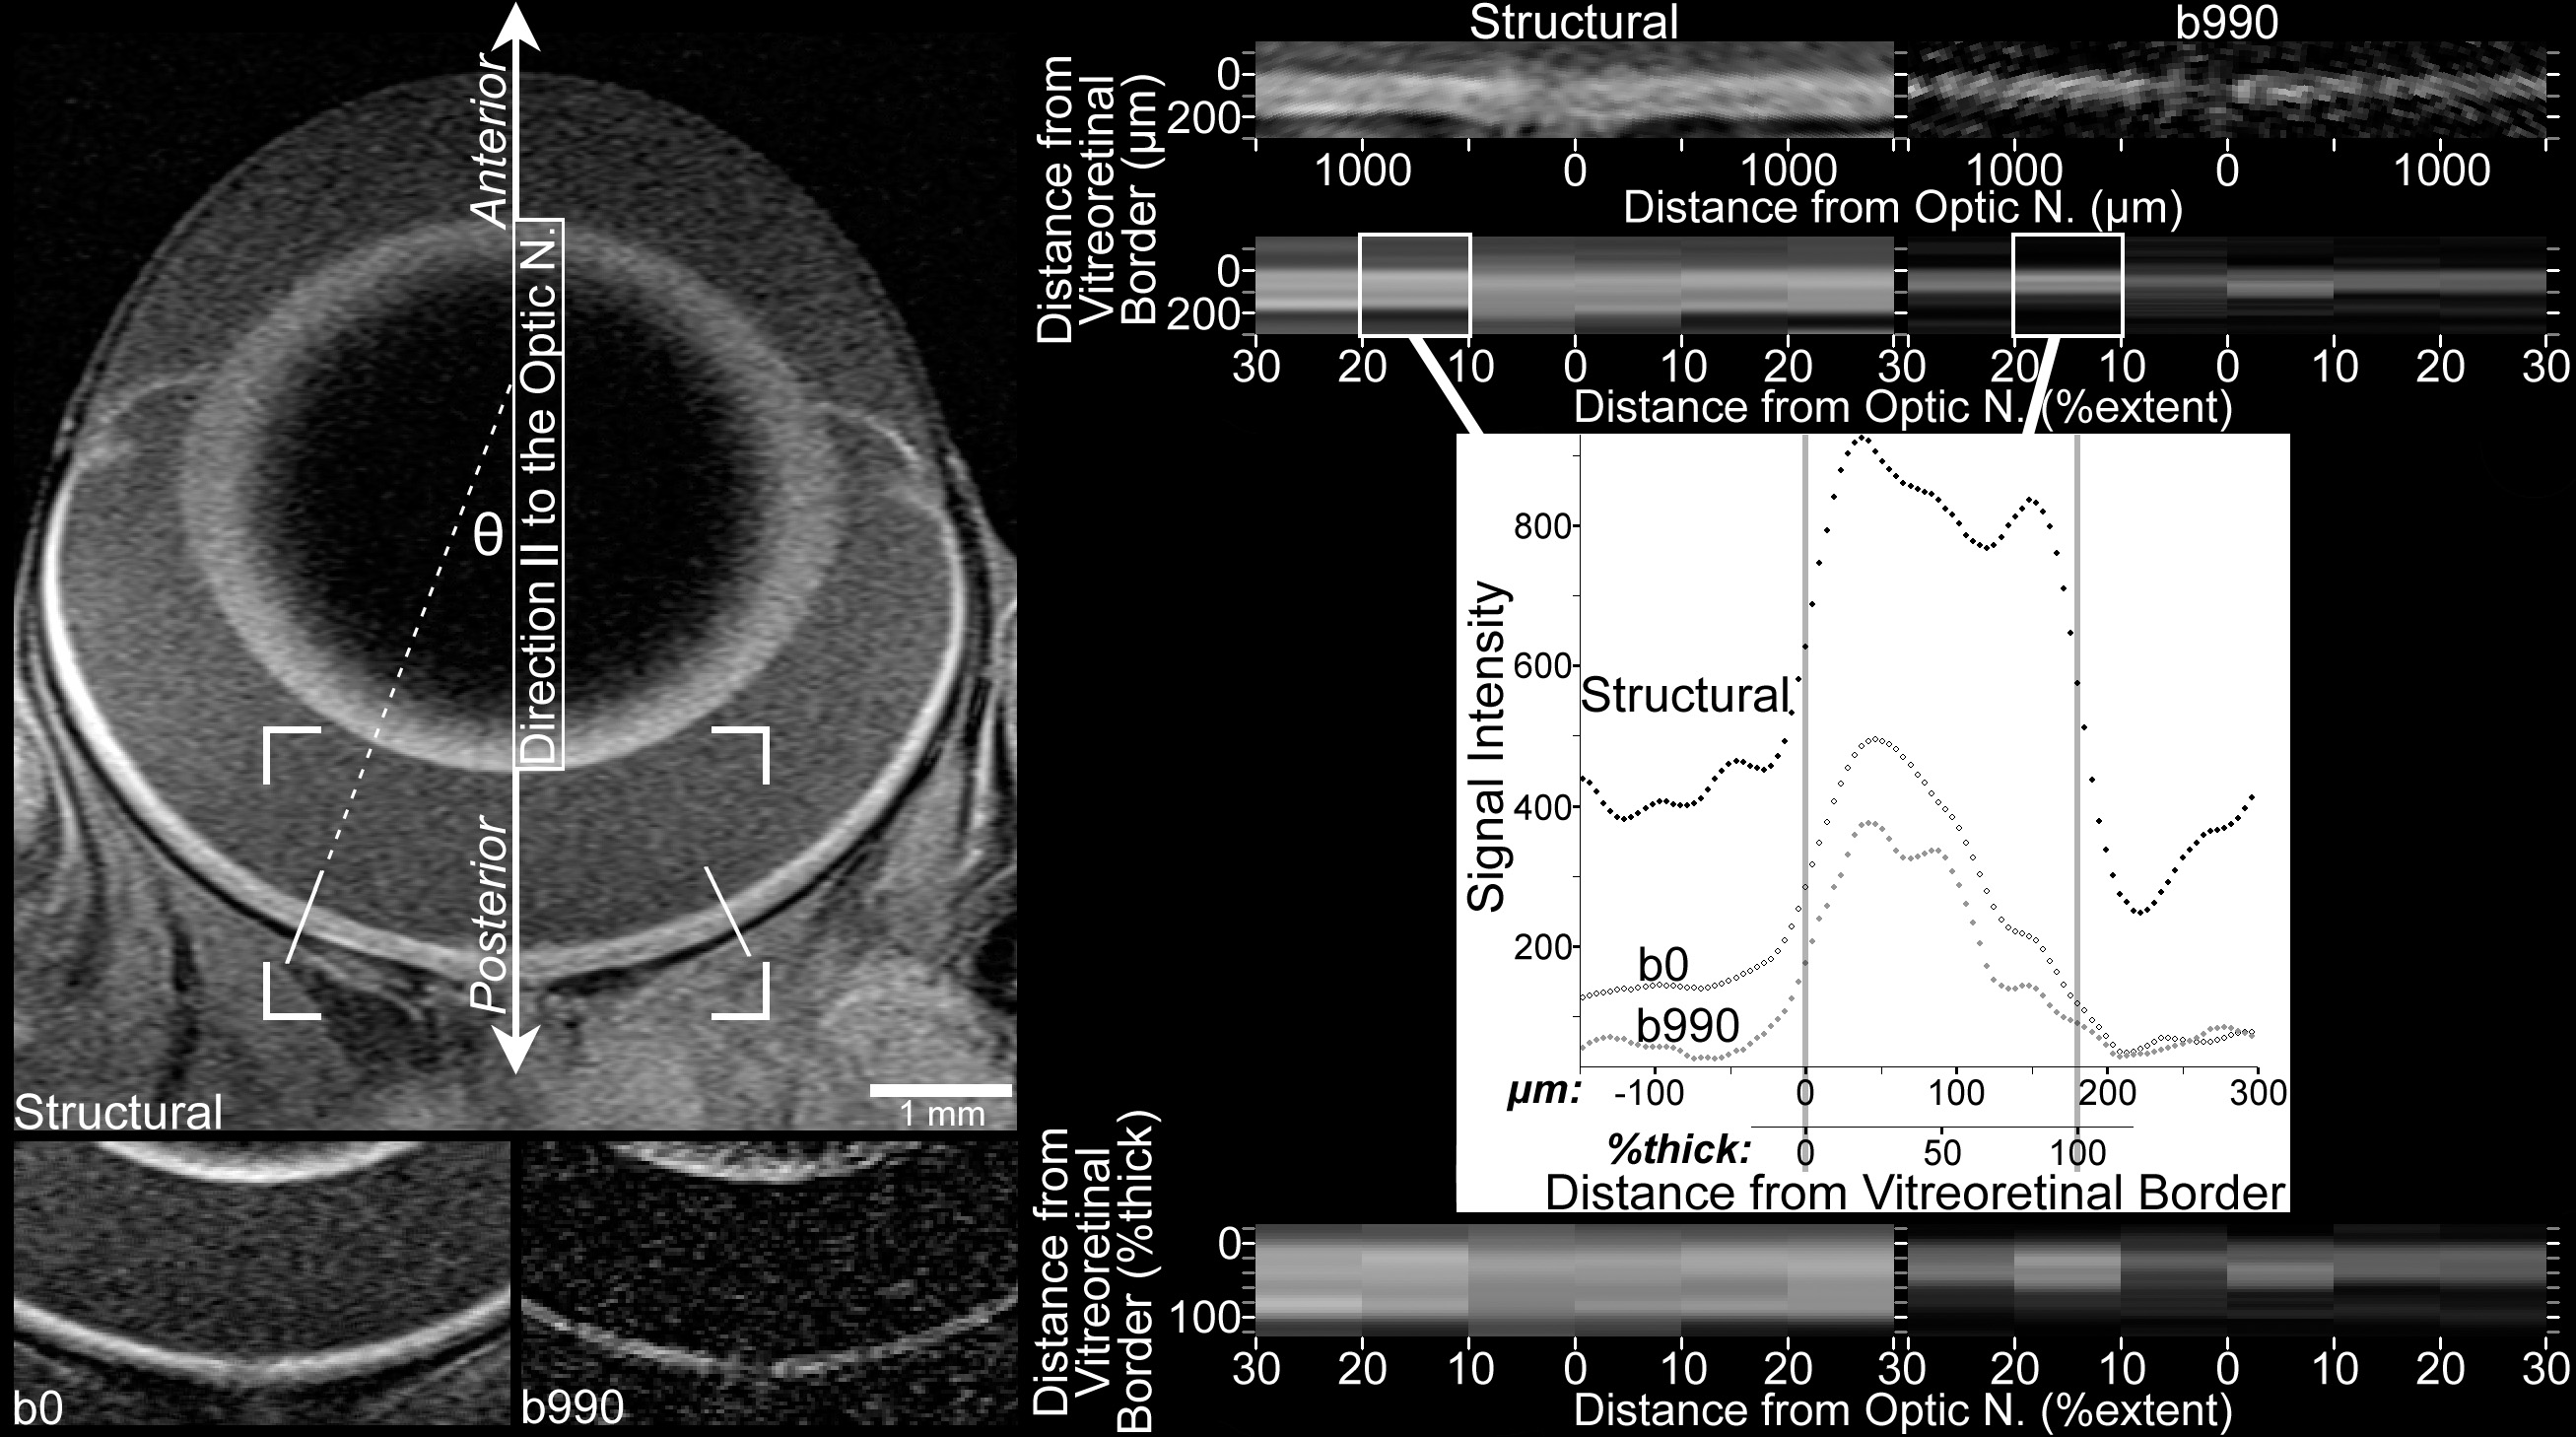

Figure 1 of Bissig, Mol Vis 2012; 18:2561-2577.

Figure 1. Image processing included linearization of the central retina, followed by spatial normalization according to location along the extent of the retina (‘%extent’) between the optic nerve (at 0%extent) and ciliary body (at 100%extent), and location within the thickness of the retina (%thick) between the vitreoretinal border (at 0%thick) and the retina-choroid border (at 100%thick). Top left: Structural image shows the orientation of the eye relative to the direction parallel to the optic nerve (║) and anterior/posterior orientation. Only the central retina is analyzed, from 10% to 30% of the hemiretinal extent (the distance, measured along the vitreoretinal border, from the optic nerve to the ciliary body). The 30%extent boundaries are indicated by solid white lines angled perpendicular to the vitreoretinal border. Cell structures of interest within the retina include the rod outer segments, which are found in the posterior outer retina and have their long axis oriented radially, relative to the center of the eye (parallel to incident light). Although the curvature of the eye produces measurements of apparent diffusion coefficient parallel to the optic nerve (ADC║) that include structures (e.g., photoreceptors) oriented off-║ by ≤θ, this should have negligible impact on ADC comparisons (see Discussion). Bottom left: Cropped images (the corners of the cropped region are overlaid on the structural image above) collected with b=0 and b=990 s/mm2 in the ║ direction. For display purposes, brightness and contrast settings are the same for all b0 and b990 images in this figure, but a different pair of brightness and contrast settings is applied to structural images. Due to resampling and averaging steps used to produce the b0 and structural images (see Methods), the b990 image best displays the native spatial resolution of diffusion images. Top right: The linearized central retina from the structural and b990 images is shown here. Since the vitreoretinal border smoothly follows the curvature of the eye, its location can be determined with accuracy in excess of the native spatial resolution: Using the images on the left, the approximate location of the border is found in several neighboring columns of voxels. A polynomial best fit to these locations specifies the vitreoretinal border. Linearized images are produced by sampling every 4.63 μm along perpendiculars to those high-order polynomials. Data in the linearized images is binned by retinal extent, and averaged within each bin. This spatial averaging improves signal-to-noise before diffusion calculations, and since it is done on linearized images, the critical spatial information—distance from the vitreoretinal border—is well preserved. Mid right (plot): Signal intensity data from the left 10%–20%extent bin is plotted to show the location of vitreoretinal and retina-choroid borders, which are determined in structural data using the half-height approach (i.e., the border is at the halfway point between local minimum and maximum) [20]. The same borders are found in the b0 profile, and are used to align b0 and structural images. As detailed extensively in previous work [4], data collected with b≥0 are then aligned to b0 data using the broad signal peak in the anterior approximately one-half to two-thirds of the retina (visible here from approximately 0 to 100 μm). Bottom right: As previously described [19], after the retinal thickness is calculated by subtracting the vitreoretinal and retina-choroid borders, the data are resampled according to distance from the vitreoretinal border relative to the retinal thickness. Finally, the resampled data (within each %extent bin, one value every 4%thick) from 10%–30%extent on each side of the optic nerve are averaged to produce a single profile, which is used for within- and across-subjects comparisons.